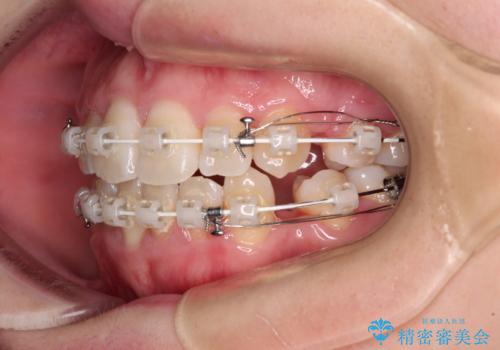

- 矯正装置

- 審美装置

舌の突出癖を改善するためのトレーニングをしっかりと行っていただいたことで、比較的スムーズに治療を進めることができました。

口元の突出感もしっかりと改善することができました。